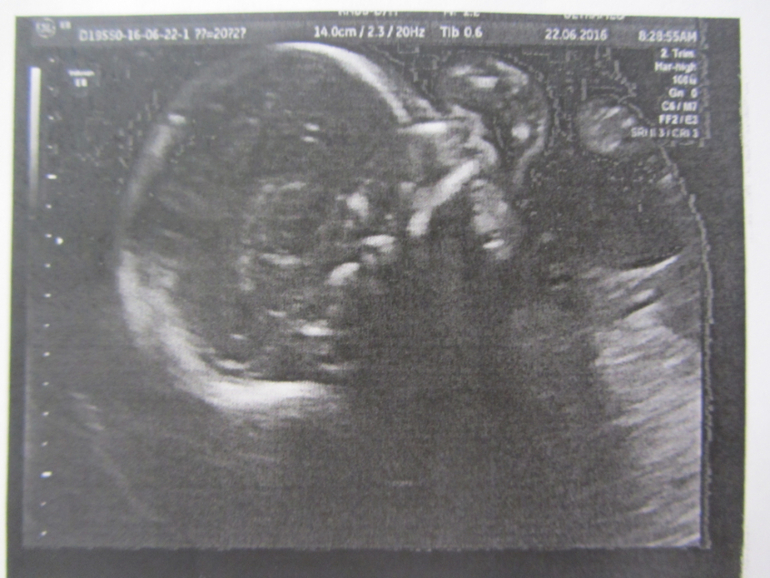

А это уже целых 20 недель :) как быстро пролетело время!